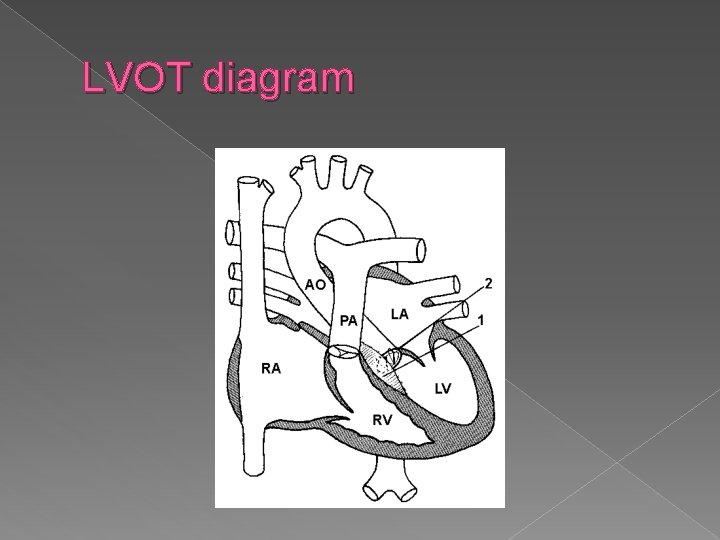

LVOT � Left ventricular outflow tract view (LVOT) › ID origin of aorta from the left ventricle › Sagittal section shows aortic arch and its branches

LVOT diagram